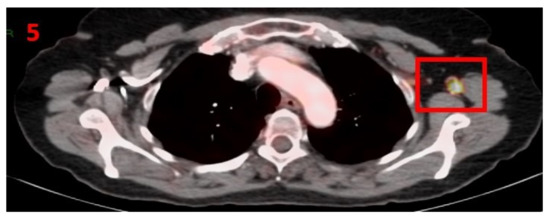

3.5. Case No 5

| Case no.5 | Colon cancer | Left arm | 12 days | Hypermetabolic uptake in the left axillary region and lymphadenopathy | Second vaccine | 8 mm | 6 | Pfizer-BioNTech |